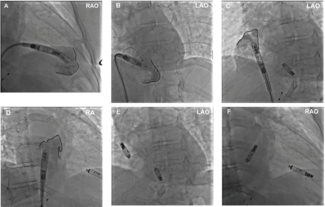

This report highlights a unique etiology, diagnostic evaluation, and management of iatrogenic atrial lead failure secondary to hemostatic surgical clip entrapment.